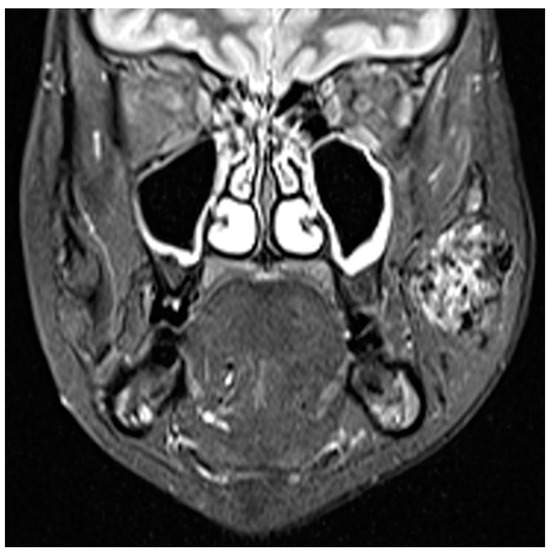

3. Vascular Malformations

3.1. Venous Malformations

3.1.1. Clinical Data

3.1.2. Diagnosis

3.1.3. Therapy